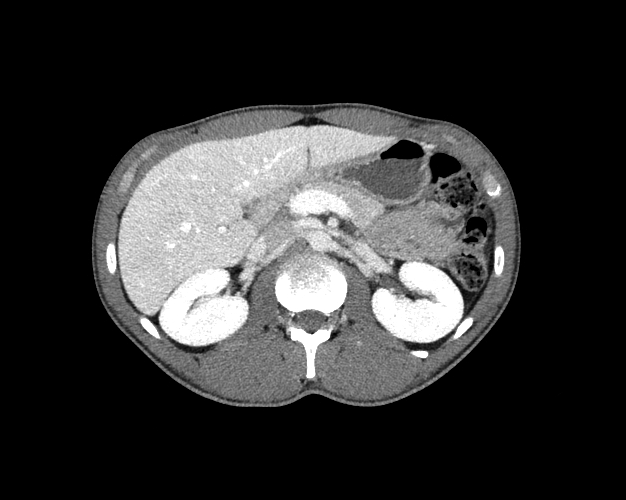

Body

Covers abdominal CT anatomy.